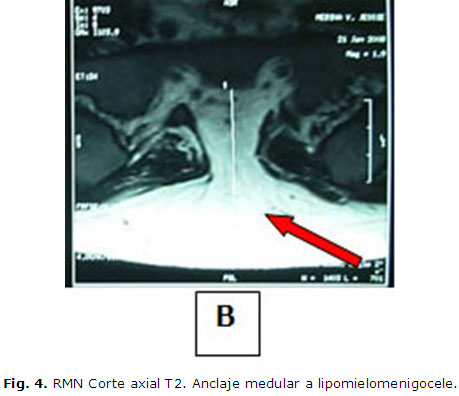

Paciente femenina de 22 años, con antecedentes de salud hasta hace dos años en que comienza a presentar dificultad para orinar, acude a la consulta de urología del Hospital "Mario Catarino Rivas". Se diagnostica una retención urinaria y se le coloca una sonda vesical de forma permanente, (Fig. 2). Es estudiada durante dos años sin encontrar una patología urológica que explique su enfermedad, por lo que se remite a consulta de Neurocirugía. Al examen físico se observa como dato positivo el aumento de volumen a nivel lumbosacro, redondeado de aproximadamente 10 cm. de diámetro, movible, no doloroso, poco adherido a planos profundos que impresionaba ser compatible con un lipoma lumbosacro. Se realiza el estudio de RMN lumbosacro, encontrándose la médula anclada en relación con la masa lumbosacra antes descrita (Fig. 3 y Fig. 4 ) (imagen sugestiva de lipomiemomeningocele). La paciente es preparada para la cirugía. Se efectúa una laminectomía lumbosacra con la resección de la masa tumoral y liberación de las adherencias del saco dural y raíces lumbosacras. Se retira la sonda vesical a las 48 horas de operada (Fig. 5) y recupera sus funciones vesicales a la normalidad. Ha sido seguida por consulta externa durante seis meses y se mantiene asintomática (Fig. 6 ). Se confirma por anatomía patológica el diagnóstico de lipoma lumbosacro.